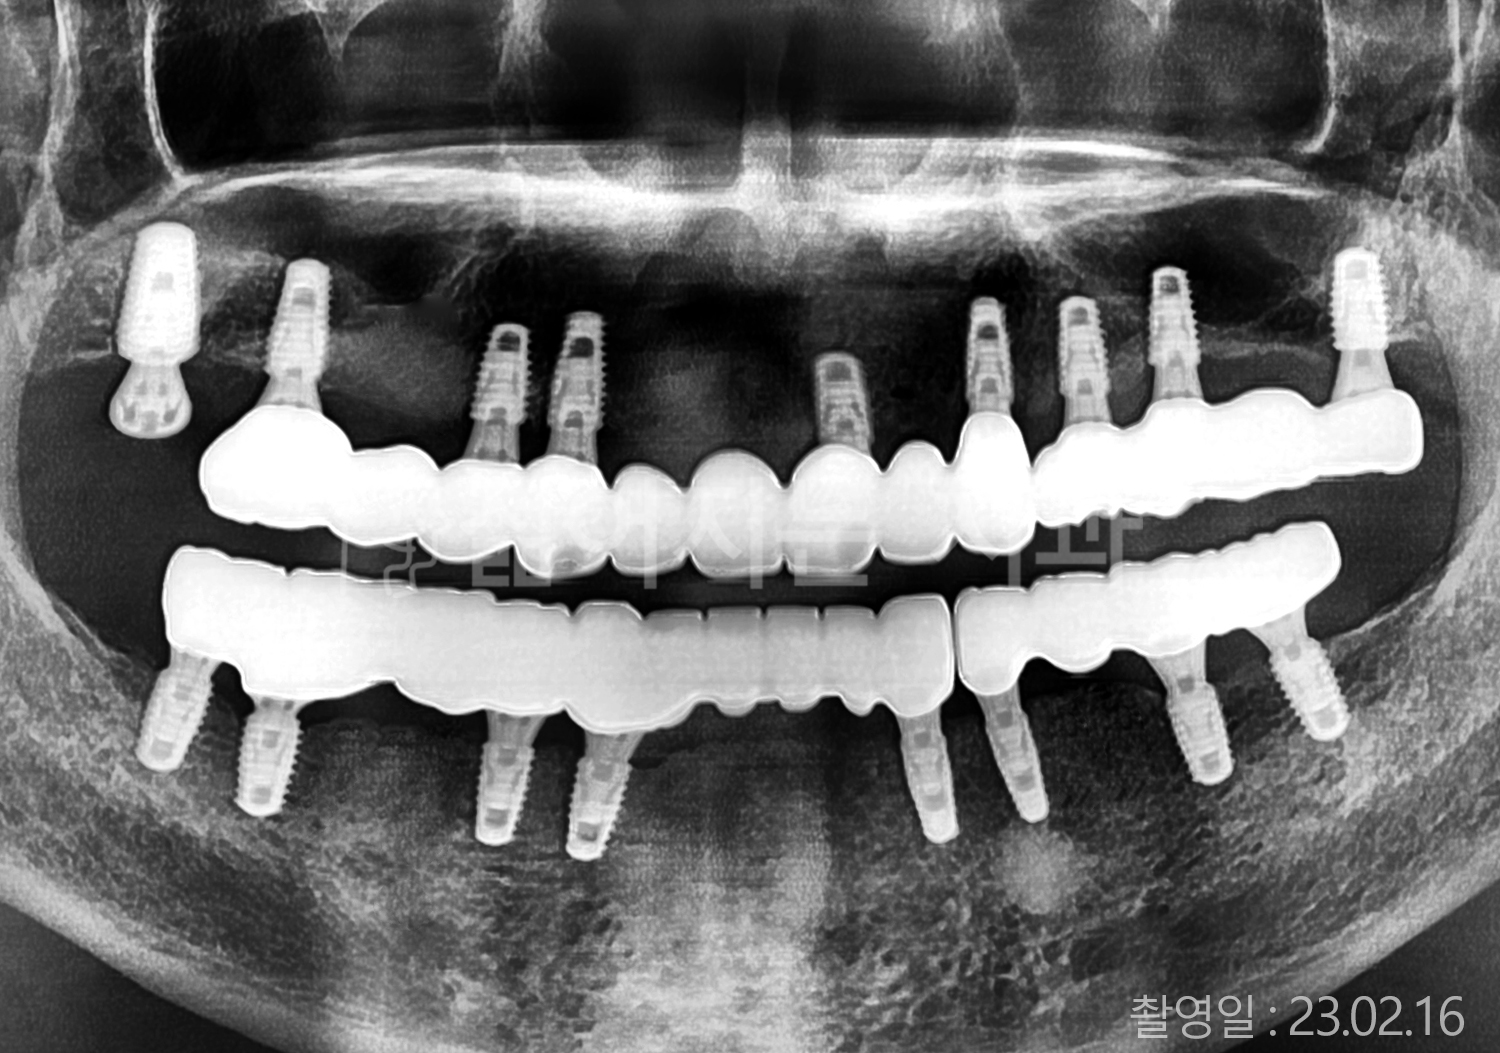

• 50대 고혈압, 당뇨, 고지혈증 전체치아 10개 이상 임플란트

• 60대 골다골증, 간경화 전체치아 10개 이상 임플란트

• 60대 고혈압, 고지혈증 전체치아 10개 이상 임플란트

• 50대 고혈압, 당뇨 전체치아 10개 이상 임플란트

• 60대 고혈압 전체치아 10개 이상 임플란트

• 60대 전체치아 10개 이상 임플란트

• 60대 고지혈증 전체치아 10개 이상 임플란트

• 40대 전체치아 10개 이상 임플란트

• 70대 전체치아 10개 이상 임플란트